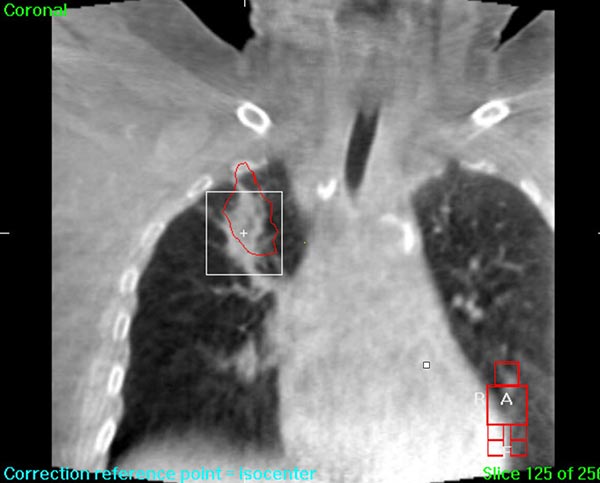

We understand that a cancer diagnosis can be scary, which is why Florida Center For Prostate Care is dedicated to compassionate care and state-of-the-art technology. Florida Center For Prostate Care uses the Elekta Synergy® machine, a digital accelerator for advanced image-guided radiation therapy (IGRT). It is the only all-digital treatment device in the world. This allows your doctor to view your tumor in real-time at the time of your treatment.

The 3-D high-quality images taken at the time of your treatment can be studied against your previous CT scans precisely and promptly to ensure that the doctors are treating your tumor as accurately as possible while greatly limiting any exposure to healthy tissue in the area.

Elekta Synergy® provides unparalleled clinical assurance to more aggressively treat tumors while keeping damage to surrounding healthy tissues to a minimum. Elekta Synergy®‘s precision accuracy reduces or eliminates the use of markers because clinicians can view soft tissue using Elekta Synergy®‘s VolumeViewTM. The low-dose imaging proficiency helps minimize the side effects of radiation therapy by decreasing the margins previously set to account for the unpredictability of target location, movement, and dimensions.